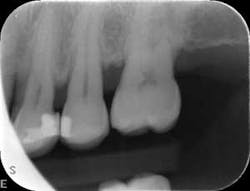

At nine months, the patient’s tissues appeared pink with no inflammation. Radiographs revealed new bone growth, especially around teeth Nos. 3, 15, and 31 (figures 10–12). The patient reported his HbA1c level stable at 8.2.

Radiographs nine months after LANAP treatment (figures 10–12)